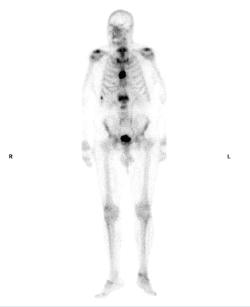

Tras los hallazgos en la TAC, surgen dudas sobre el diagnóstico y se completa el estudio con una resonancia magnética (RM) (Figura 3) en la que se corrobora la presencia de una fractura vertebral sobre un cuerpo vertebral peculiar. Sin embargo, en la secuencia STIR no se aprecia el edema que se esperaría en una fractura aguda. También se observa una marcada hipertrofia de los elementos vertebrales posteriores, cierta captación al nivel de las apófisis articulares, así como el aspecto heterogéneo del cuerpo vertebral. Todos estos hallazgos radiológicos apuntan a la posibilidad de estar ante una fractura crónica sobre una vértebra patológica, concretamente se sospecha que pueda ser una enfermedad de Paget vertebral (EP).

Figura 3. Resonancia magnética de columna lumbosacra, secuencia STIR. Corte sagital: hiperintensidad tenue y difusa en L1 con ocupación del canal > 50%. Cortes axiales: focos de lisis y esclerosis en diferentes niveles del cuerpo de L1, hiperintensidad en el pedículo izquierdo, típico de fractura crónica.